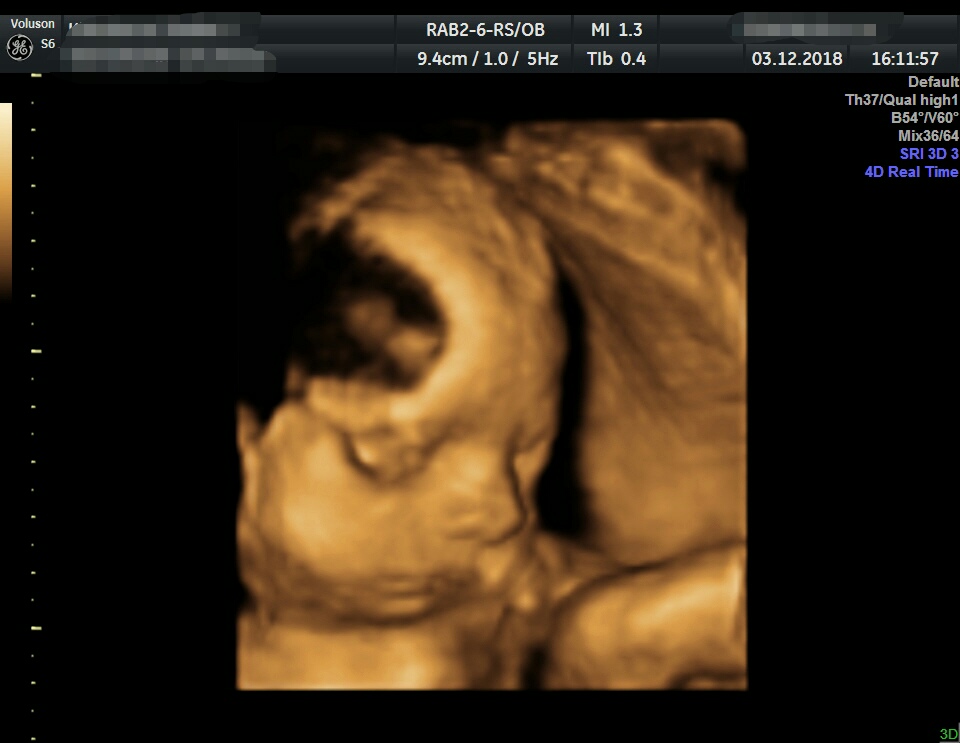

Holky, tak dnes jsme byli na 3D a oba dva byli úplně špatně natočeni, takže nemáme ani fotku ani video. Manžel naštvanej, že jsme tam strávili hodinu a půl a nic, ptže si myslel, že nám aspoň řeknou, jak jsou velcí atd. Ale naštěstí po nás paní doktorka nic platit nechtěla, když nic vidět nebylo.

@stef9328 mala je tam krasne